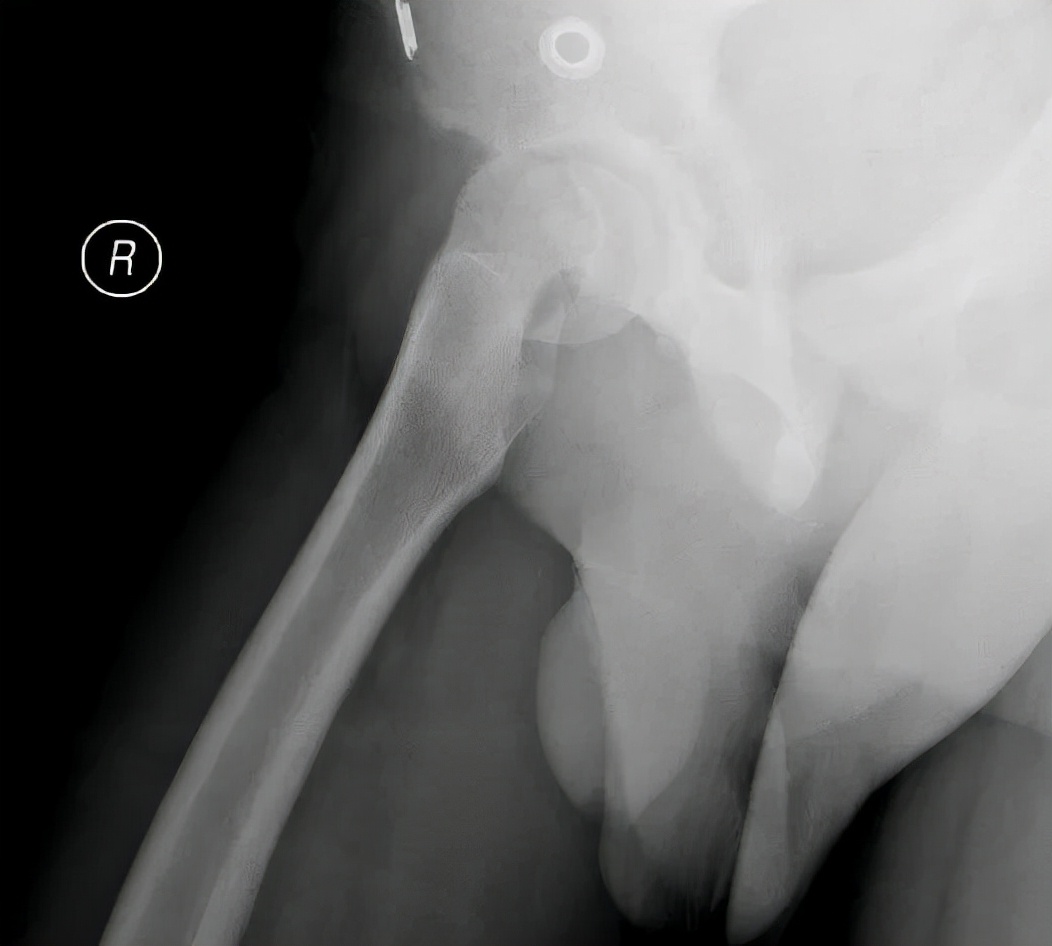

病例1 男,13岁,左侧重度SCFE

病例1 髋关节外科脱位,改良Dunn截骨,术后2年,X线示位置良好,无股骨头缺血坏死